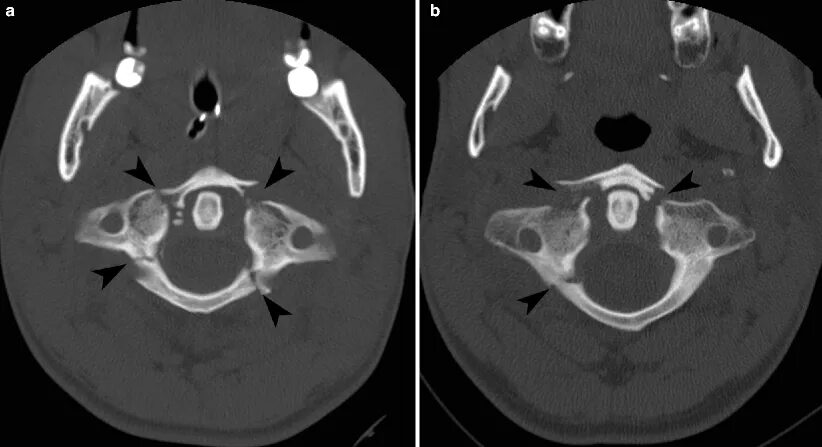

Атлант кт